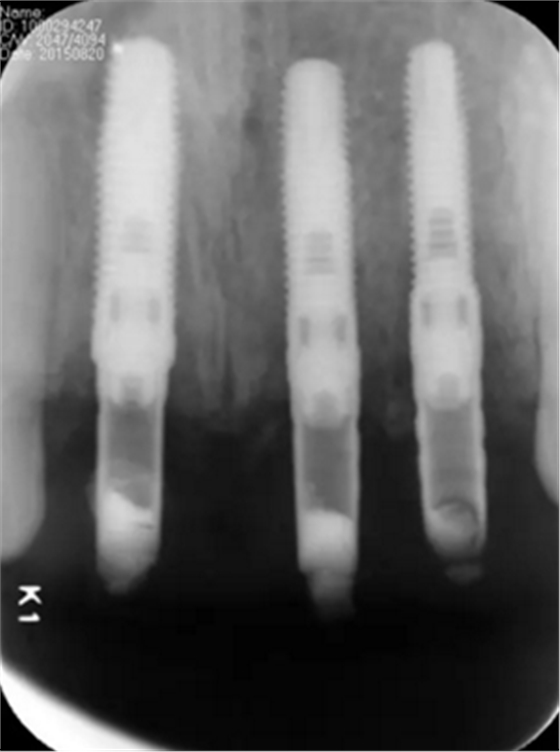

(2)即刻种植、即刻临时修复。术中不翻瓣微创拔除牙根,牙槽 窝骨壁完整。在多级导板辅助下完成种植窝洞制备,植入Bego柱形种植 体,型号分别为:上颌右侧中切牙位点4.1mm×15mm、上颌左侧中切牙 位点?3.75mm×15mm、上颌左侧侧切牙位点3.25mm×15mm,扭矩均为 35N·cm。种植体与唇侧骨壁间隙约2mm,植入Bio-Oss®Collagen骨胶 原。戴入桥用钛临时基台,临时冠就位顺利,自凝树脂口内粘接后适当修整 外形,充分磨光,调 至正中 、前伸 和侧方 与对颌牙均无接触。术后 根尖片显示种植体位置、方向良好。

图13 术后即刻根尖片